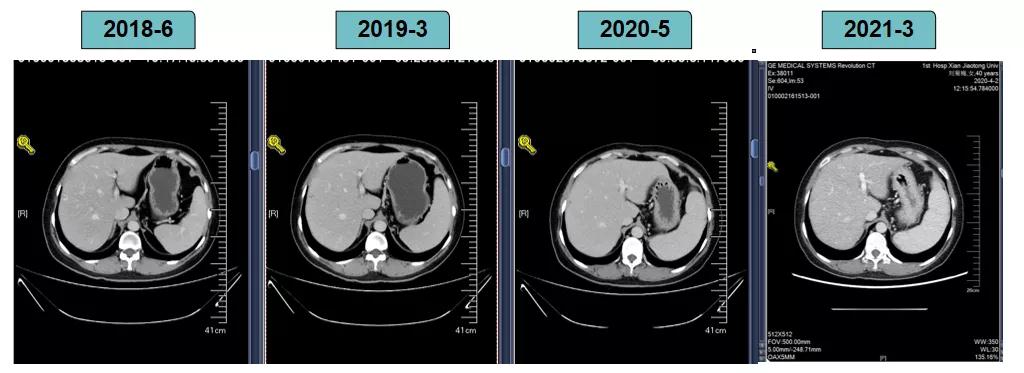

胸腹部增强CT示(2018-6-28):胸骨后占位,肝内异常强化灶,腹膜后肿大淋巴结。

2018-7-17成功入组ELAINA临床研究(试验方案编号:BO29919),IWRS分配随机号3210。于2018-7-17开始接受T-DM1 3.6mg/kg(252mg)治疗,并间断对其进行疗效评估。现阶段患者PFS达近40个月。

靶病灶:腹主动脉左侧和下腔静脉右侧淋巴结

非靶病灶:肝左叶、肝右前叶下段;纵膈胸骨后淋巴结节;前上纵膈淋巴结;腹膜后小淋巴结

影像学评估-纵膈淋巴结:

影像学评估-肝脏:

影像学评估-腹膜后淋巴结: